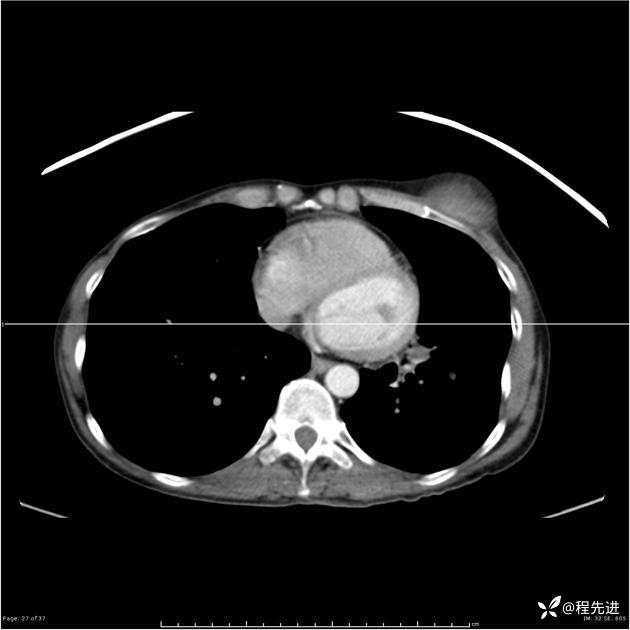

病例女,53岁,气管、左主支气管、下叶支气管内结节,乳头状瘤?期待你的精彩解读

女,53岁

乳头状瘤?